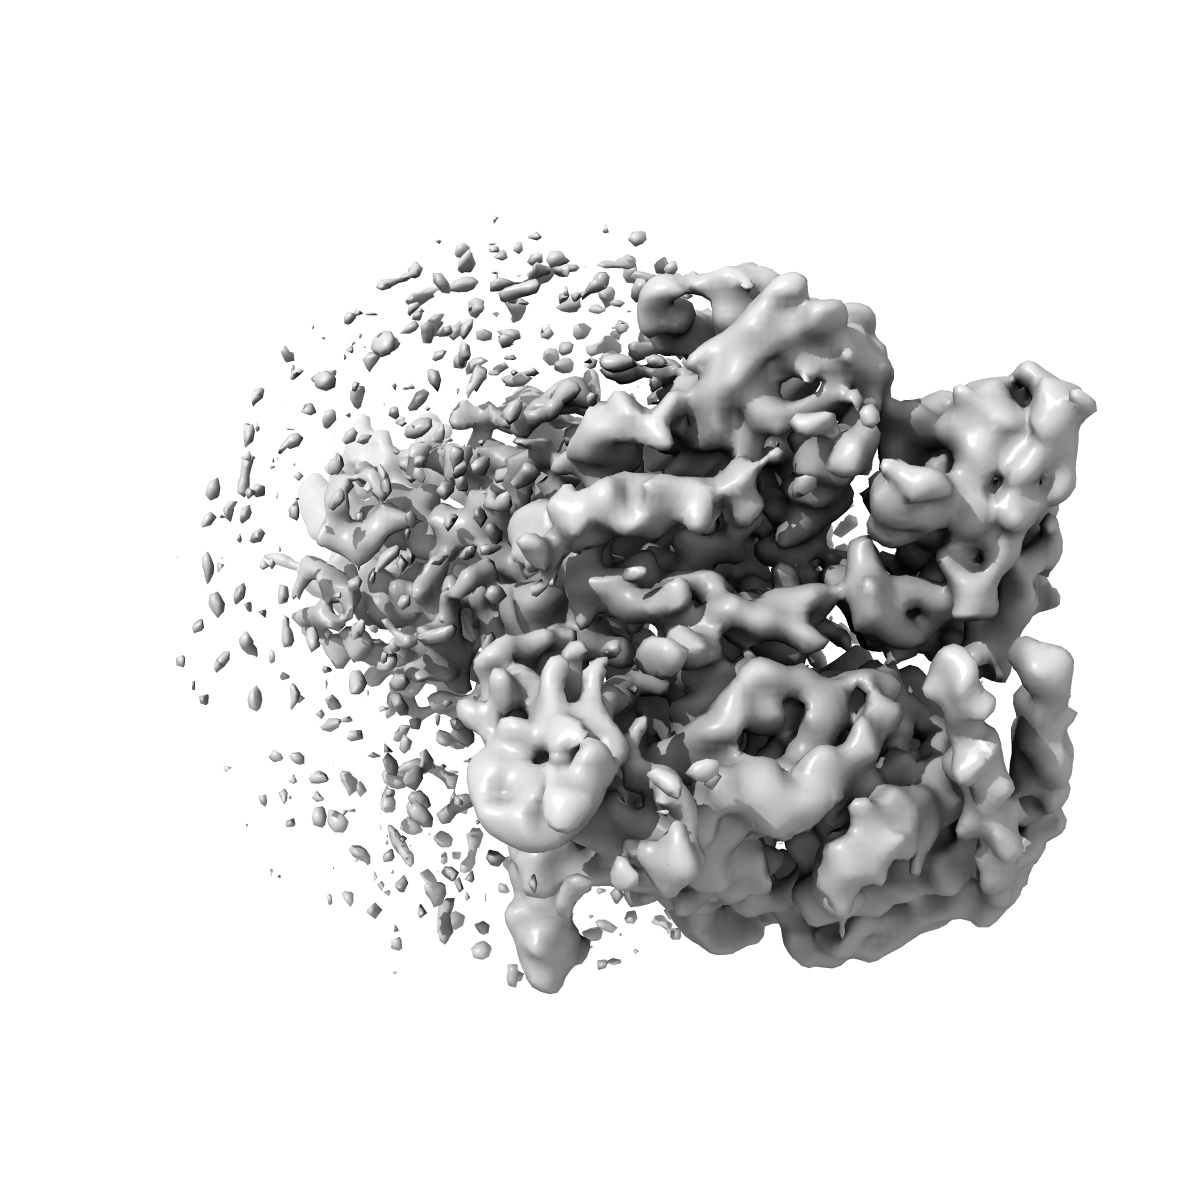

Cryo-EM structure of parathyroid hormone receptor type 1 in complex with a long-acting parathyroid hormone analog and G protein

Single-particle4.0 Å